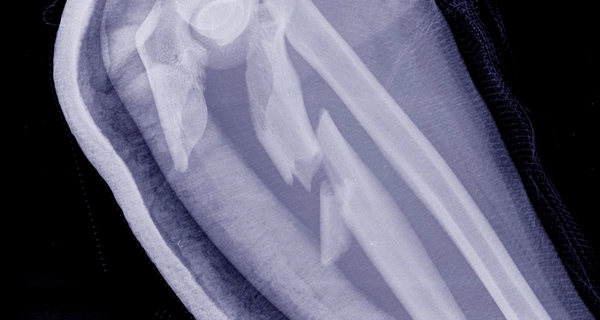

Рентген суставов — это надёжный метод диагностики, позволяющий оценить состояние суставных поверхностей, хрящей и костей. Исследование помогает выявить артрит, артроз, вывихи, подвывихи, последствия травм, а также возрастные изменения суставов. Процедура проводится быстро, безболезненно и с минимальной лучевой нагрузкой.

Снимок позволяет врачу определить наличие изменений, связанных с травмами или хроническими заболеваниями, и подобрать правильное лечение.